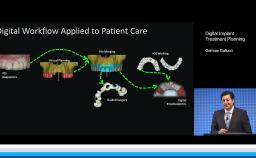

This presentation introduces and addresses the physiologic changes that occur in the oral cavity with age. Particular focus is given to the dental and periodontal tissues, oral mucosa, salivary glands, and the alveolar process (or alveolar bone). A differentiation is made between changes associated with age and those associated with pathology or therapy, particularly in regard to bone. General considerations are provided regarding treatment planning of elderly patients for dental implants.

- discuss the influence these changes may have on planning for implant placement and restoration